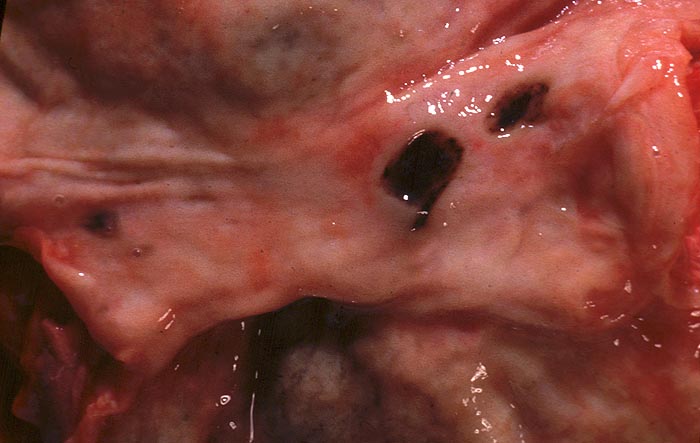

Florides chronisches Magenulkus

Das akute Ulkus ist rund, oval oder seltener polyzyklisch begrenzt und liegt meist im Schleimhautniveau. Das chronische Ulkus ist häufig kreisrund und im Längsschnitt trichter- oder treppenförmig. Die Schleimhautränder können lippenförmig über den Ulkusgrund hinausragen. Palpatorisch ist das chronische Ulkus aufgrund der narbigen Fibrose induriert. Die Schleimhautfalten laufen sternförmig auf das Ulkuszentrum zu. Das chronische Ulkus tritt zu 10%, das akute zu 25% multipel auf. Mikroskopisch zeigt das chronische Ulkus eine typische Schichtung (s. Bilder). Die Gefässe im Ulkusgrund zeigen eine starke Intimaproliferation mit teilweiser oder vollständiger Obliteration der Gefässlichtung. Morphologische Veränderungen in der übrigen Magenschleimhaut geben einen Hinweis auf die Ätiologie des Ulkus (Typ B oder C Gastritis).

• Antrumschleimhaut mit chronischer Gastritis am oberen Rand des Ulkus.

• Schichtung: Detritus, oranges Quellungsfibrinoid, Granulationsgewebe, Narbe.

• Im Ulkusgrund arrodierte Arterie mit Intimafibrose und Abscheidungsthrombus.